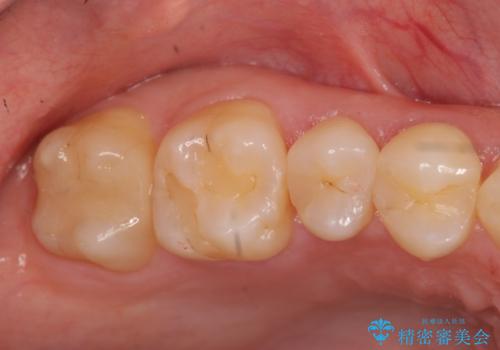

奥歯の虫歯治療でしたが、プラスチック周りと、歯と歯の間が大きな虫歯になっていました。

インレーでの修復予定でしたが、歯と歯の間が狭く、正確な型取りが難しい状態でした。

そこで、部分矯正を行い、歯の間を広げてしっかりした歯型を取りました。